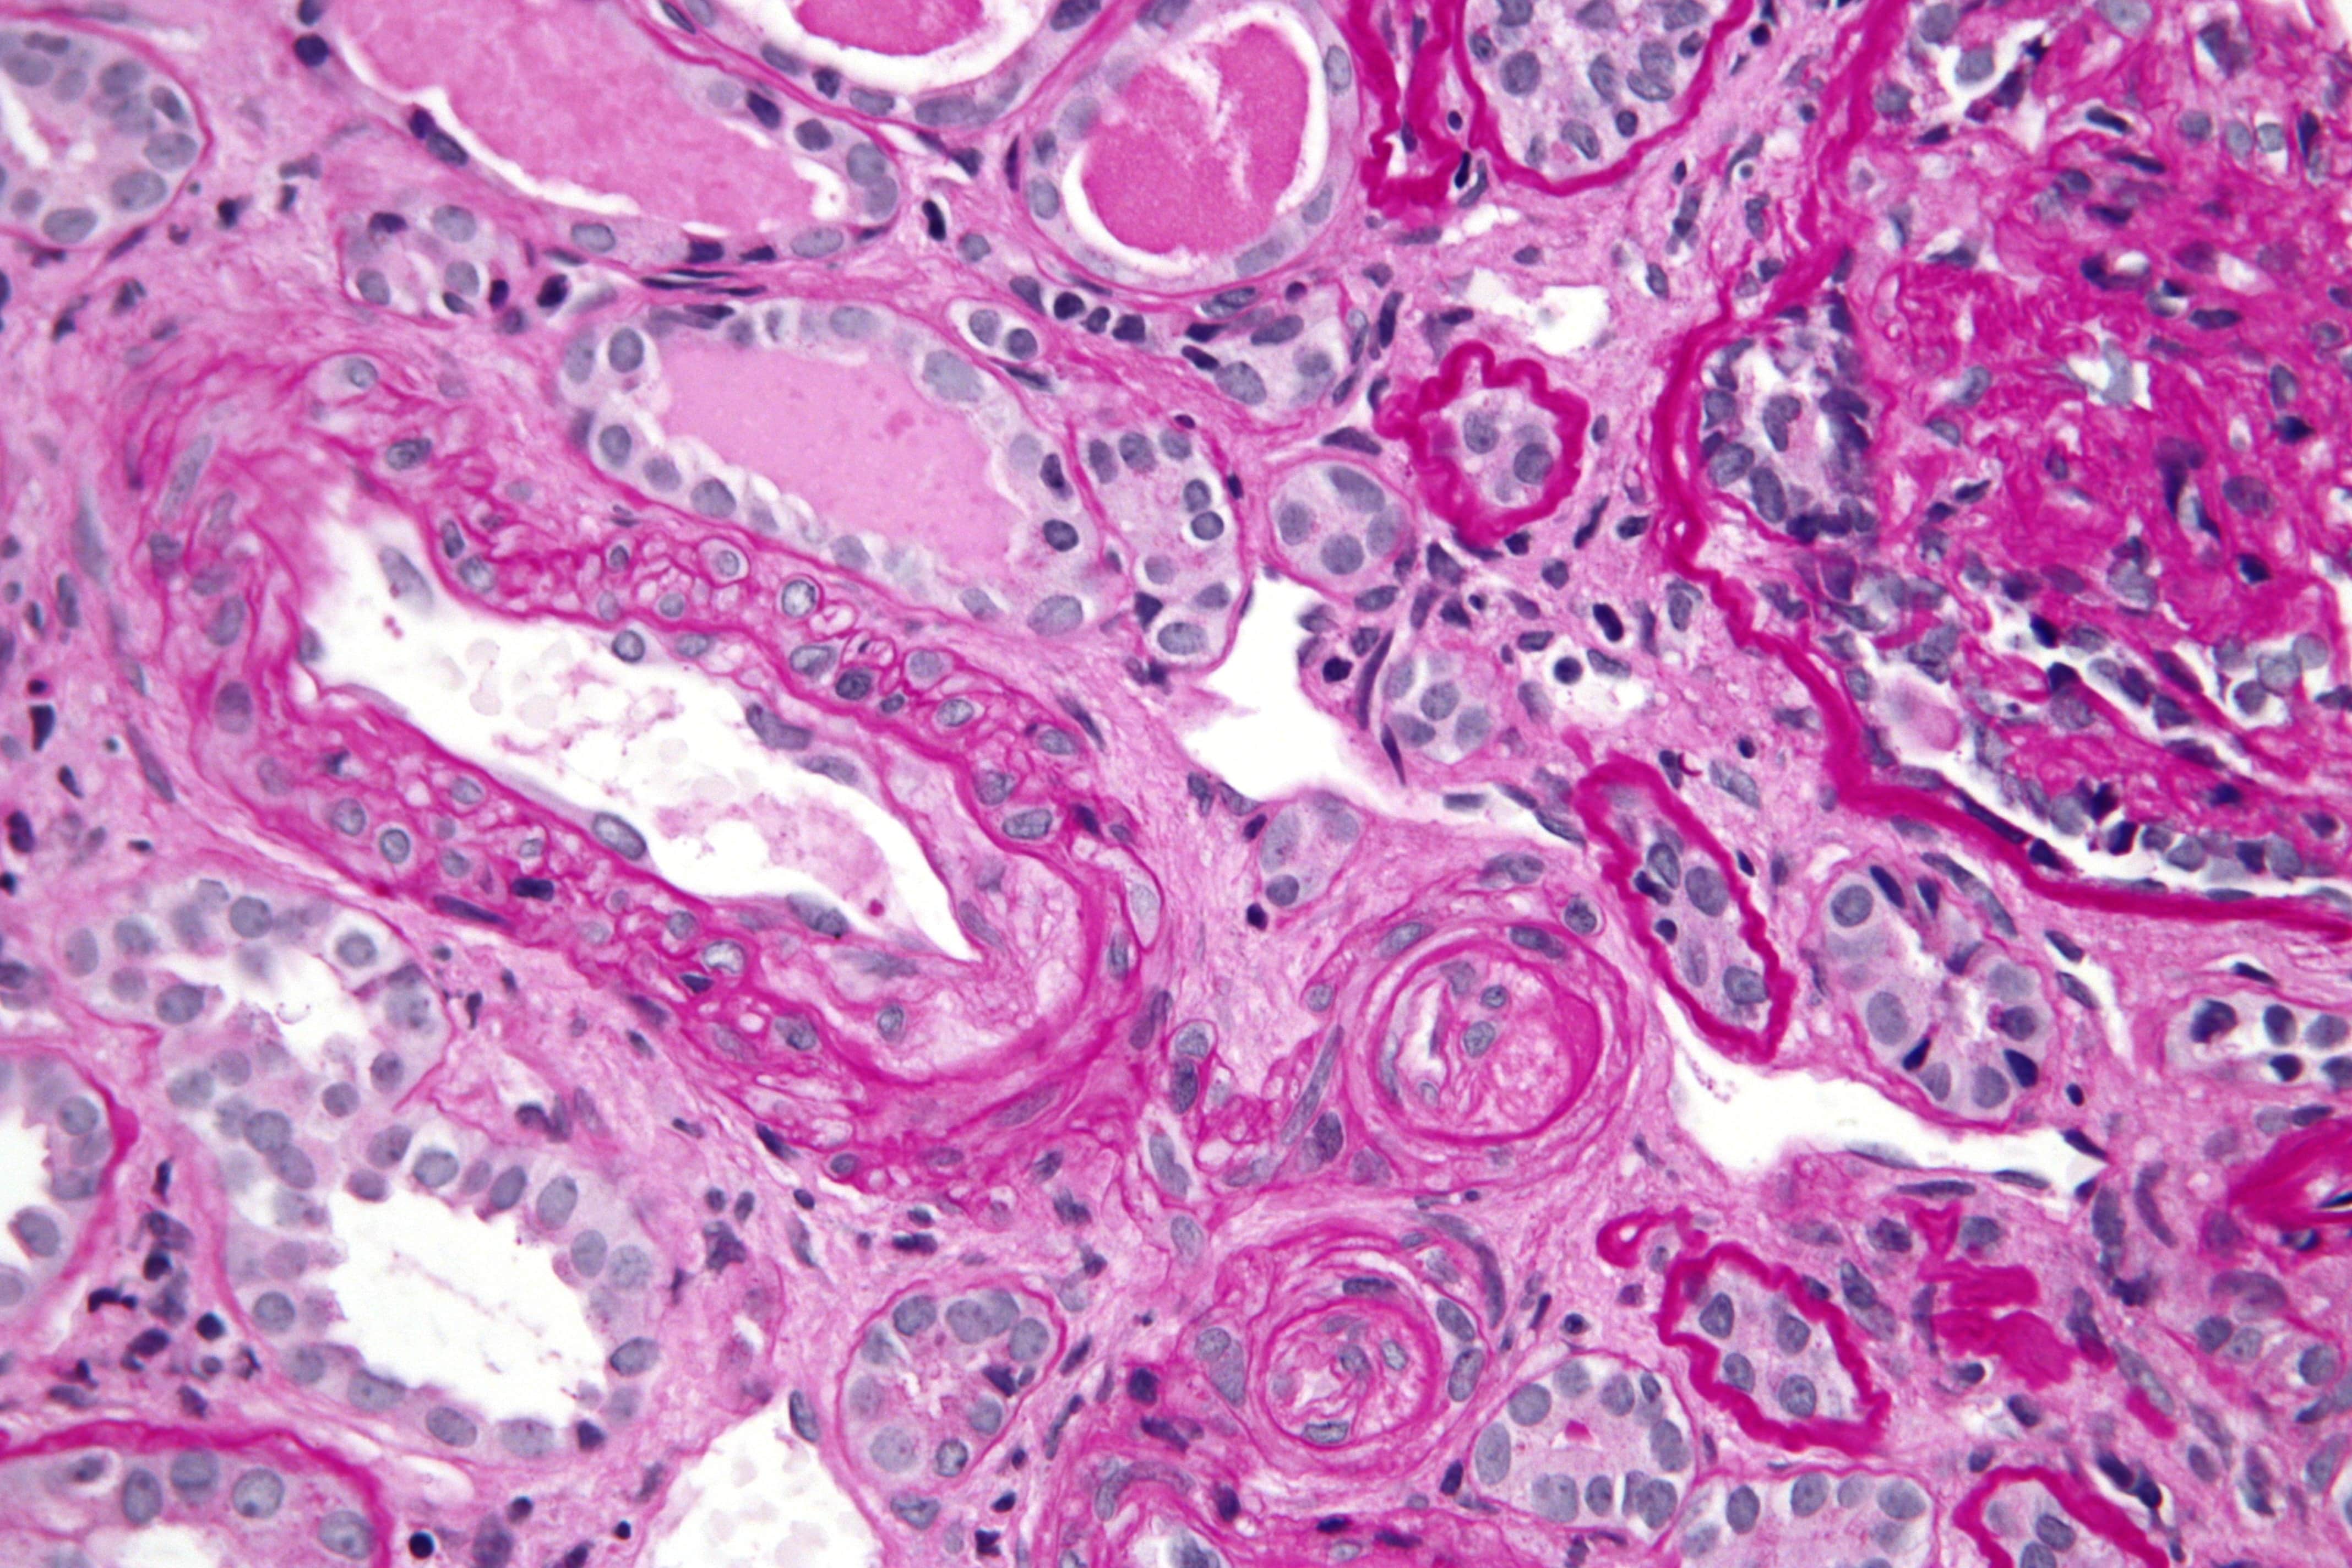

शिल्पा शेट्टी ने एप्ला नाम की जिस बीमारी का जिक्र किया वो अधिकतर महिलाओं में पाई जाती है। इस बीमारी का पूरा नाम है एंटीफोसफोलिपिड सिंड्रोम। मैक्स अस्पताल में प्रसूति एवं स्त्री रोग विशेषज्ञ डॉक्टर तान्या बख्शी रोहतगी कहती हैं, “एंटीफोसफोलिपिड सिंड्रोम एक ऑटो इम्यून बीमारी है। इसमें हमारा शरीर ऐसी कोशिकाएं बनाता है जो स्वस्थ कोशिकाओं पर हमला करके उन्हें खत्म कर देती हैं। ऑटो इम्यून में एक ऐसी खराबी पैदा हो जाती है जिससे असामान्य कोशिकाएं शरीर के थक्के जमने की प्रक्रिया पर हमला करने लगती हैं। इससे खून में जल्दी-जल्दी थक्के जमने लगते हैं।”

इस सिंड्रोम का असर शरीर की धमनियों, नसों और अंगों पर पड़ता है। उनमें खून के थक्के जमने से रक्तप्रवाह में बाधा आती है और अंगों में समस्याएं आने लगती हैं। इसके कारण गर्भ, किडनी, फेफड़े, दिमाग, हाथ-पैर आदि अंग प्रभावित होते हैं जिससे गर्भपात, अंगो का निष्क्रिय होना और आघात जैसी दिक्कतें हो सकती हैं। डॉक्टर तान्या बताती हैं, “ये समस्या महिला और पुरुष दोनों में होती है। कई बार बच्चों को भी हो जाती है। लेकिन ये ज्यादातर महिलाओं में ही देखने को मिलती है।” डॉक्टर तान्या रोहतगी के मुताबिक महिलाओं में ऑटो इम्यून संबंधी बीमारियां ज्यादा पाई जाती हैं। ऐसा होने का कारण आनुवांशिक भी हो सकता है और हार्मोनल भी। महिलाओं के शरीर में मौजूद हार्मोन जैसे इस्ट्रोजन आदि के कारण भी उनका खून गाढ़ा होता है और थक्के जमने का खतरा ज्यादा होता है।

एप्ला सिंड्रोम के गर्भधारण पर असर पड़ने से गर्भपात हो सकता है, बच्चा अविकसित पैदा हो सकता है या मृत बच्चा भी पैदा हो सकता है। डॉक्टर तान्या रोहतगी ने बताया, “हमारे शरीर में छोटी-छोटी रक्तवाहिनियां (नसें) हैं जिनमें ये थक्के बनने लगते हैं। गर्भ में बच्चे को विकसित होने के लिए निर्बाध रक्त प्रवाह चाहिए होता है ताकि उसे पर्याप्त पोषण मिल सके। लेकिन, खून में थक्के जमने से रक्त प्रवाह में रुकावट आ जाती है और बच्चे को पोषण नहीं मिलता, वो विकसित नहीं हो पाता। इससे गर्भपात हो सकता है। गर्भपात शुरुआती महीनों में या बाद के महीनों में भी हो सकता है। जिन महिलाओं में गर्भपात नहीं होता उनमें प्लेसेंटा पर छोटे-छोटे थक्के जमने की वजह से बच्चा विकास नहीं कर पाता और वो छोटा या अविकसित पैदा होता है। उनका वजन काफी कम हो जाता है। बच्चा समय से पहले भी पैदा हो सकता है। प्लेसेंटा से ही बच्चे पोषण प्राप्त करते हैं। कुछ मामलों में जब बच्चे का पोषण बहुत ही कम हो जाता है तो वो गर्भ के अंदर ही मर जाता है। ऐसे में बच्चा मृत पैदा होता है।”